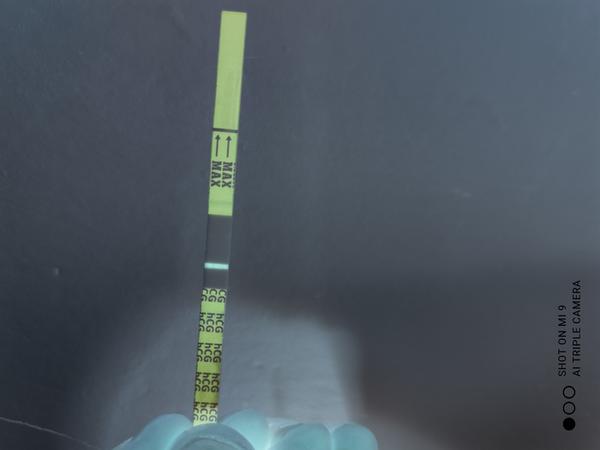

Je to duch či ryska?

Ahoj je to duch či ryska? Skúšala som to dať i do negatívu. Mám 10 dní od styku.

Tak ja patrím k tým čo má asi dobré oči 🤣 na každej fotke vidím samozrejme slabulinko ale niečo tam je ak to je do ružová tak sa ale neteš moc ešte stále nemáš nič vyhráte .o 2 dní testuje verím že tie čo nevidia už uvidia

@noemikatka robila si aj dnes test????? Lebo mne mama test nikdy ducha nespravil. Iba vtedy bola slaba ciarka ked som mala biochemicke ☹ ale toto vyzera na peknu ciarku...tak drzim.palce. Mne na 9dpo okrem mamatestu ukazal aj ten najlacnejsi zo stranky Adiel.

Teraz vidim nieco velmi.slabe ked som na inom svetle...ako som uz pisala, mama test mi nikdy neduchoval, mala som vrlmi slabu ciarku v den menstruacie a bolo z toho biochemicke. Nechcem ta znepokojovat ale ak mas pravidelne cykly /28-30 dni/ tak na 4.den meskania by uz ciarka mala byt ovela silnejsia. Ak nemas,tak este skus zajtra alr iny test a naj z ranneho moču aj ked mne na 10 dpo ukzal aj pepino z poobedneho moču.